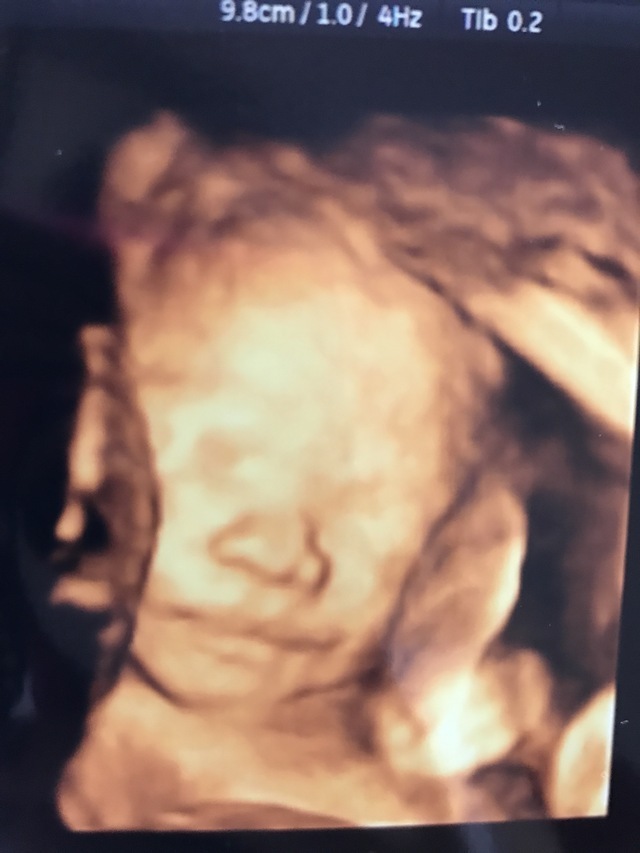

24週6日(24w6d・男の子)|diamond さん(31歳)

エコー写真撮影時のエピソード:

4Dでリアルに見れる為、毎回妊婦健診が楽しみでした。 この写真は私に似てると言われました。

産まれてから改めて見直しましたが、今の我が子はこのエコー写真のままで、最近の技術は本当に凄いね!!とみんなで感心しています。